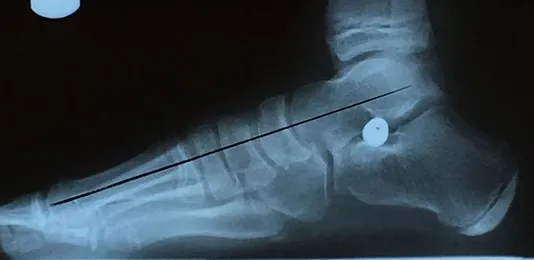

Pre and Postop X-rays Subtalar Joint Implant (Below)

Patient JD